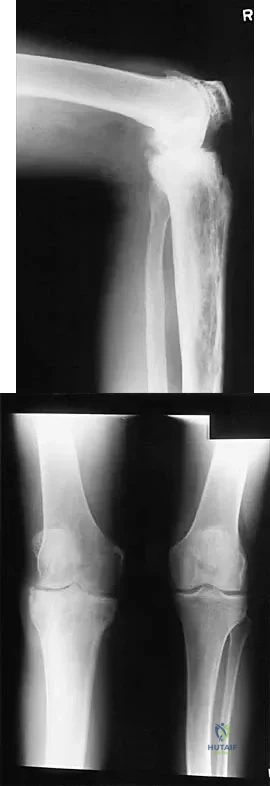

Figure 19 shows the radiograph of a 45-year-old woman who has a painful nonunion. Treatment should consist of

The radiograph reveals a reverse obliquely subtrochanteric/intertrochanteric fracture. Open reduction and internal fixation should be accomplished with a 95-degree fixed angle device. An intramedullary nail with screw fixation into the head is another possible technique. Either method should correct the varus deformity. Exchange of a high-angled screw and plate device to a longer side plate and bone grafting does not afford any improvement in the mechanical stability. Hardware removal and retrograde intramedullary nailing is not indicated for this level of a proximal femoral injury. Placement of an implantable bone stimulator may change local biologic factors but would not enhance mechanical stability. The patient's femoral head is intact without signs of collapse; therefore, hardware removal, proximal femoral resection, and total hip arthroplasty are not warranted. Haidukewych GJ, Israel TA, Berry DJ: Reverse obliquity fractures of the intertrochanteric region of the femur. J Bone Joint Surg Am 2001;83:643-650.